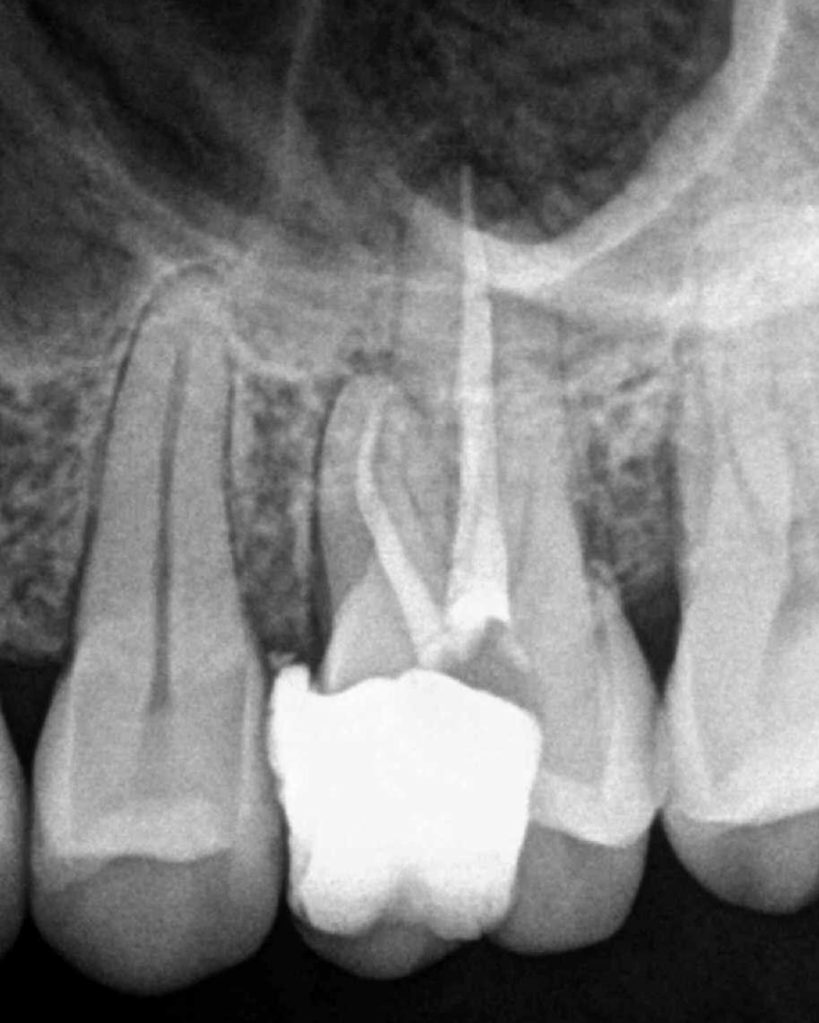

Molar gran curvatura bifurcación palatino